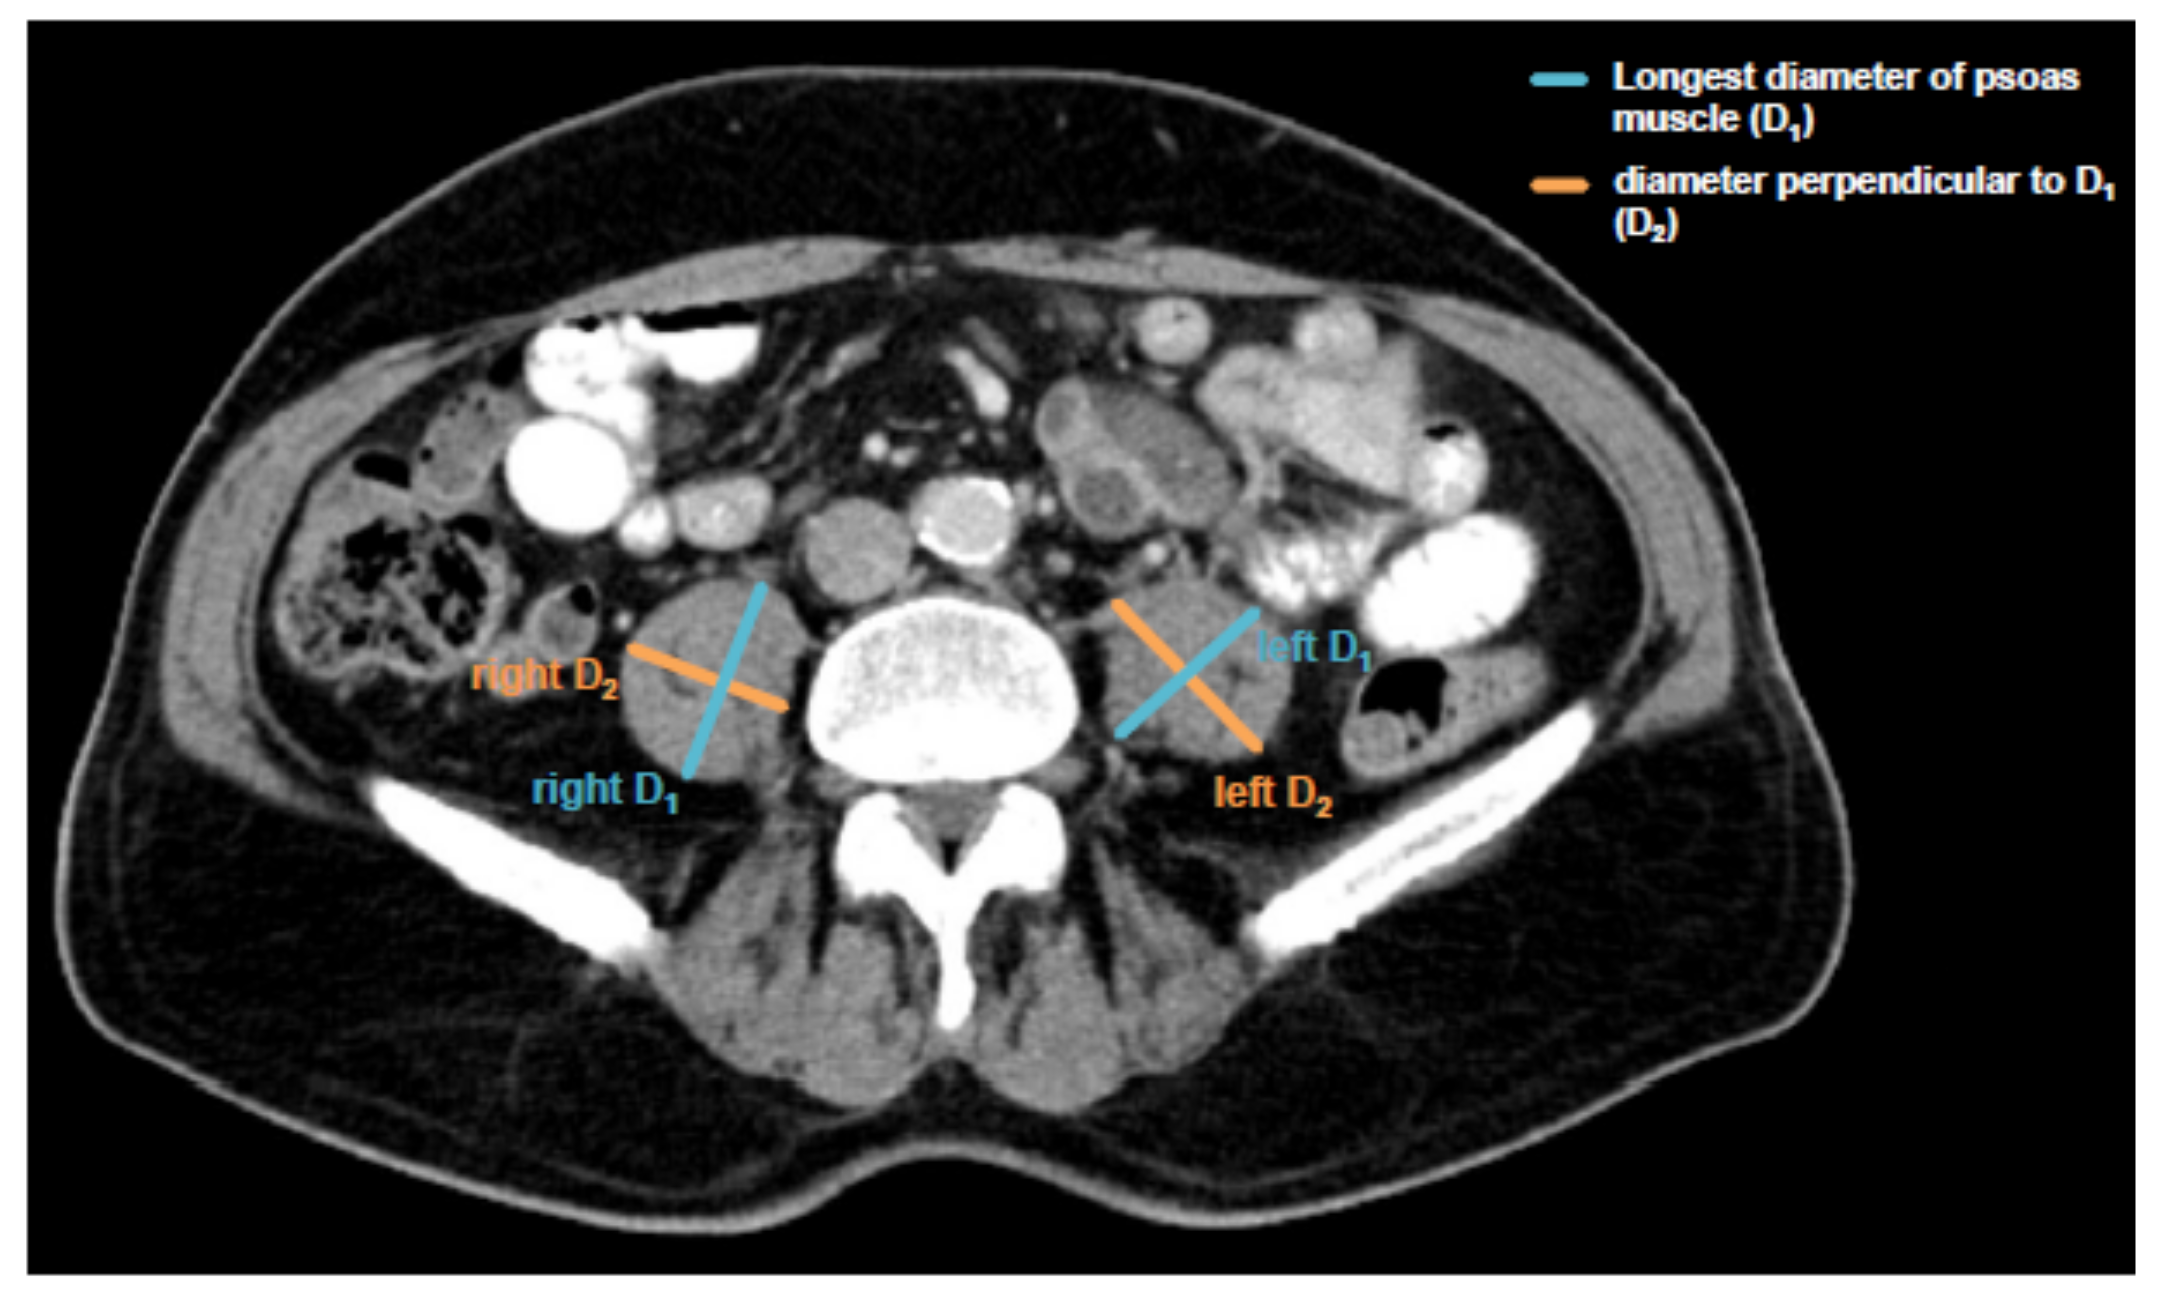

2.4. Assessment of Sarcopenia and Psoas Muscle Index